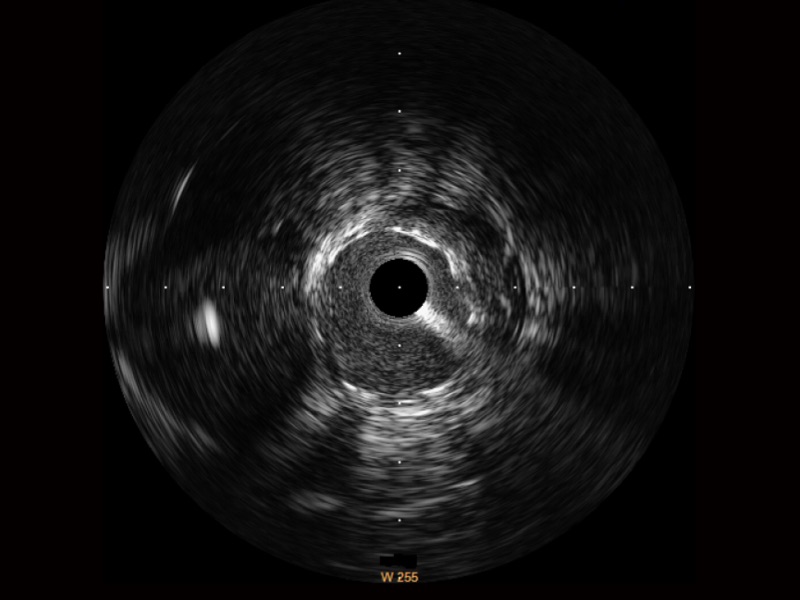

開立寬頻IVUS圖像

傳統(tǒng)IVUS圖像

對比傳統(tǒng)IVUS導管成像,開立寬頻IVUS圖像的近場支架梁顯影更細膩,遠場中膜外血管仍清晰可辨,兼顧遠中近,兼顧分辨力與穿透深度